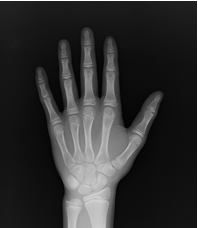

骨年齢を割り出す方法はいくつかありますが、基本的に左手のレントゲン写真(図)を使い、手を構成するいくつかの骨の形状から骨年齢を割り出します。

• 暦年齢、骨年齢とも12.4歳

図)アカデミー試験での骨年齢評価のための左手レントゲン写真。すべて小学6年生で、暦年齢はほぼ同じですが、レントゲン写真でも明らかなように手を構成する骨の成熟に違いがあるのがわかります。骨年齢は10~13.3歳と幅がみられています。